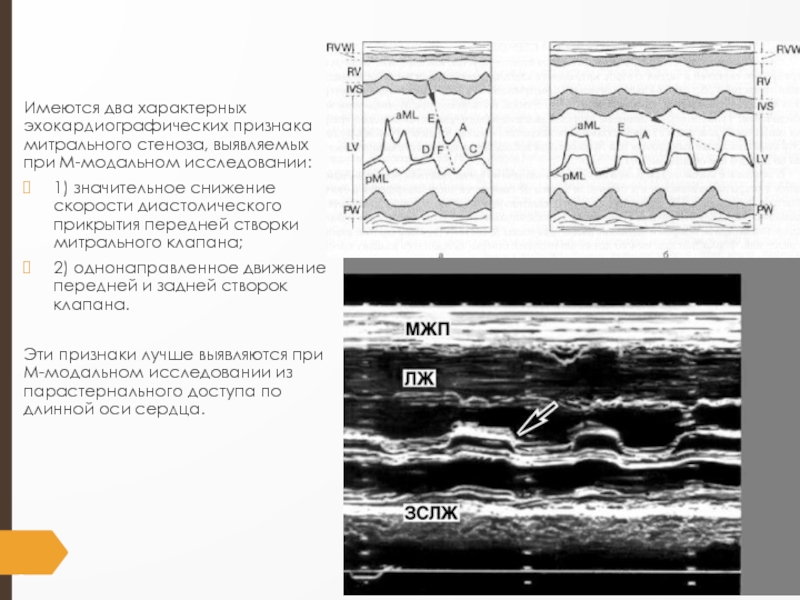

Слайд 13Имеются два характерных эхокардиографических признака митрального стеноза, выявляемых при М-модальном

исследовании:

1) значительное снижение скорости диастолического прикрытия передней створки митрального

клапана;

2) однонаправленное движение передней и задней створок клапана.

Эти признаки лучше выявляются при М-модальном исследовании из парастернального досту­па по длинной оси сердца.